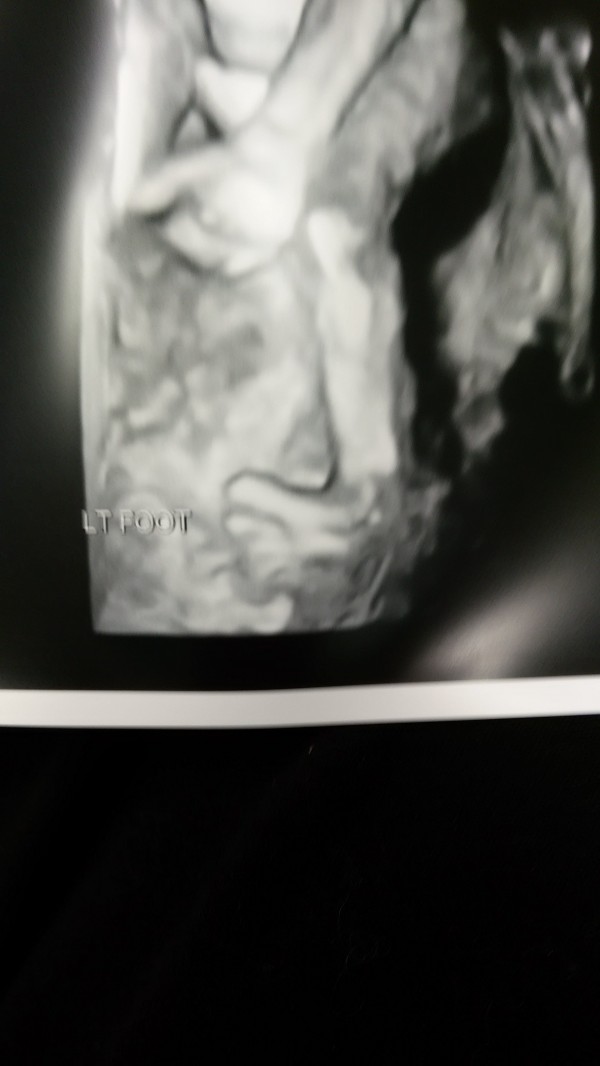

The first is his left foot. They are both turned in but that's the only picture they could get. The second needs no explanation lol

And you were certain it was going to be a girl lol. That is definitely a penis!

lol I know. I was so shocked I started crying. I'm glad I was wrong though!